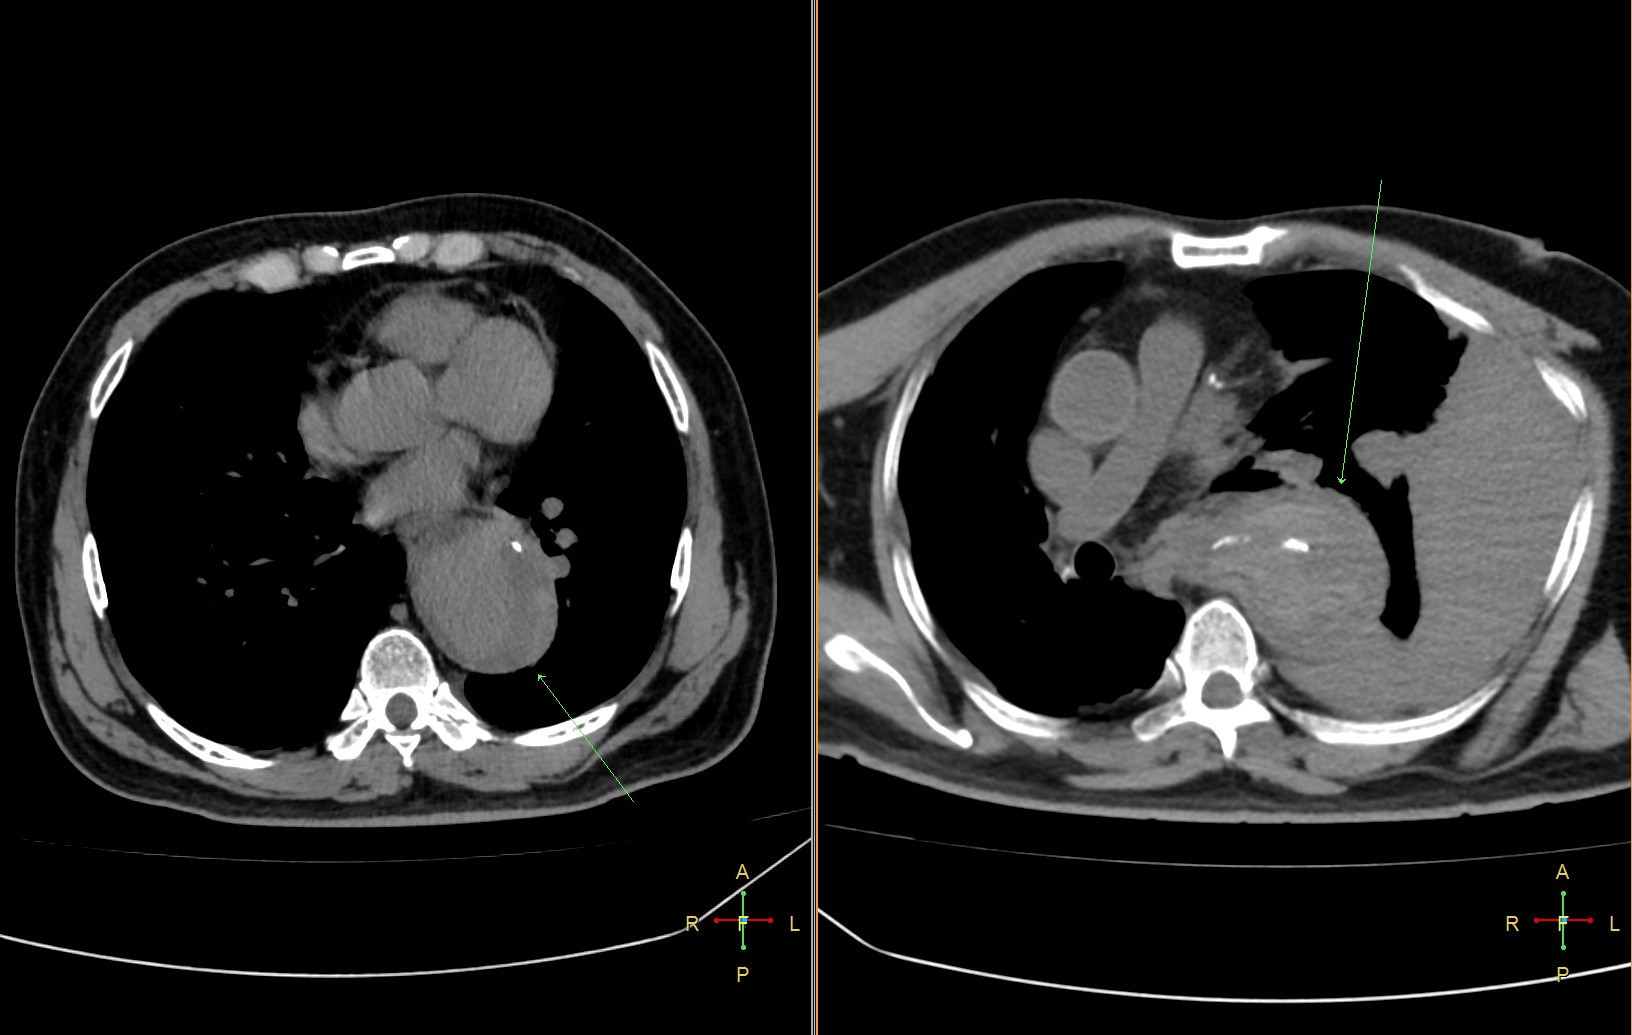

- Phình động mạch chủ dọa vỡ: Đau tại vùng có túi phồng là dấu hiệu cảnh báo động mạch chủ sắp vỡ. Viêm quanh túi phình gây đau âm ỉ, có thể rò rỉ vào các tạng xung quanh (ống tiêu hóa, phổi). Đây là một cấp cứu ngoại khoa hoặc can thiệp. Các thăm dò chức năng cận lâm sàng như CT động mạch chủ ngực và siêu âm Doppler bụng có thể giúp chẩn đoán và điều trị.

- Bóc tách thành động mạch chủ: Là một biến chứng nặng nề, điều trị phức tạp, chẩn đoán xác định bằng chụp CT động mạch chủ.